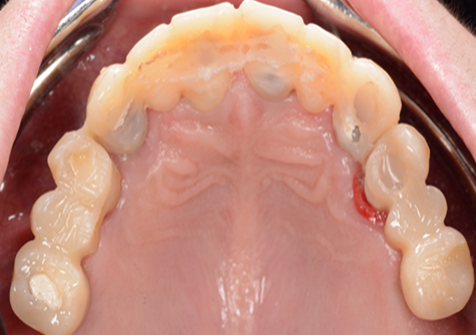

Clinical case: Advantage of fuse abutment with AnyRidge implant for immediate loading in

upper fully edentulous case

- Courtesy of Dr. Kwang Bum Park -

“AnyRidge shows excellent initial stability

& stable results after immediate loading in

upper fully edentulous case. ”